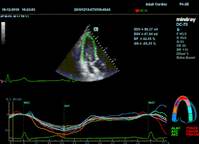

Всё изменилось с появлением технологии Speckle-tracking. Ультразвуковые приборы компании Mindray DC 8, 70, 80, Resona 6,7 оснащены данной функцией. Для использования необходим ЭКГ-канал. В чем же смысл данного технологического новшества? Прибор использует видео петли сечений миокарда, разбивает миокард на точки со стабильной визуализацией – speckle, и затем производит слежение каждой точки в течении нескольких сердечных циклов. Изменение пространства между точками дает нам представление о возможностях деформации миокарда, как продольной – Longitudinal Strain, так и деформации скручивания – торсии и Radial Strain.

Как работать с данным методом? Для Longitudinal Strain необходимо записать видео петли апикальных сечений в память прибора: 4С, 3С, 2С. Для повышения качества трекинга рекомендуется производить запись на выдохе пациента. Затем произвести разметку по линии эпикарда, перикарда и центра миокарда. Нажатием кнопки «начать слежение» активируется программный алгоритм, видео петля оживает вместе с размеченными точками-speckle’ами. При необходимости производится коррекция. После анализа всех трех сечений можно получить данных продольной деформации как в среднем значении, так и по каждому сегменту миокарда левого желудочка. Нормальным показателем считается Longitudinal Strain -20%. Нижней границей -14%.

Видео примеры на приборе Mindray DC 70